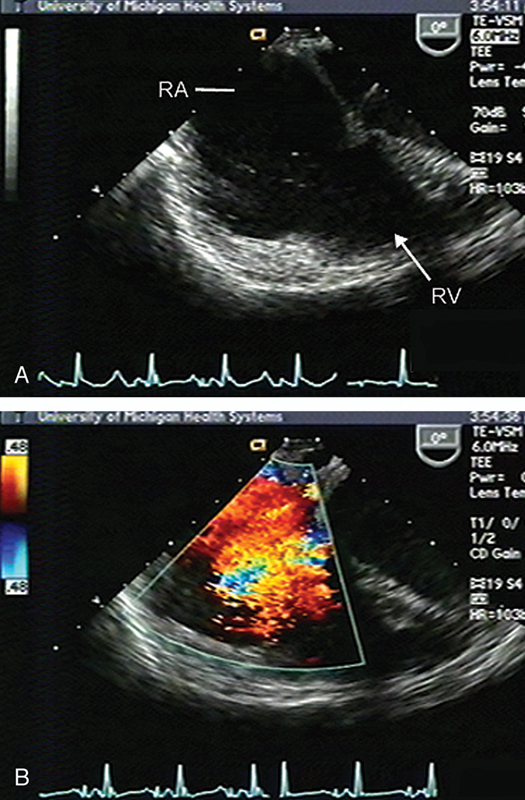

فحوصات تشخيصية لبعض امراض القلب والشرايين التاجية